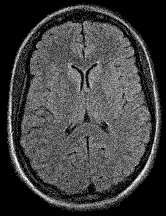

In Figure 1 we show a toy example of misjudgments that occur when evaluating the quality of a 2D MRI scan compared to degraded versions of the same image with the selected measures. PSNR even yields the same value for all the very different degradations, and all of the tested measures fail in the judgement of massive local information loss (d), as well as in the judgment of stochastic noise (e) versus block artefacts (f). This toy example served as an inspiration to study the behavior of the standard measures in real-life medical imaging tasks.

Refer to caption

(a) Reference I𝐼Iitalic_I

(b) (22.6, 0.97, 0.01)

(c) (22.6, 0.92, 0.01)

(d) (22.6, 0.98, 0.08)

(e) (22.6, 0.64, 0.39)

(f) (22.6, 0.63, 0.27)

Figure 1: Illustrative toy example of problems occuring when using the standard FR-IQA measures PSNR/SSIM/LPIPS for the evaluation of medical images. Degradations have been added artificially to the reference (a) MRI scan: contrast enhancement (b), brightness change (c), hole (d), Gaussian White noise (e), jpeg compression (f). PSNR yields the same value for all degradations, SSIM and LPIPS fail to identify the hole (d), and misjudge the quality of (e) and (f).